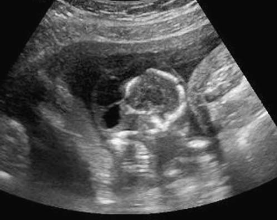

An oblique sonogram of the fetal abdomen most likely demonstrates:

multicystic dysplastic kidney